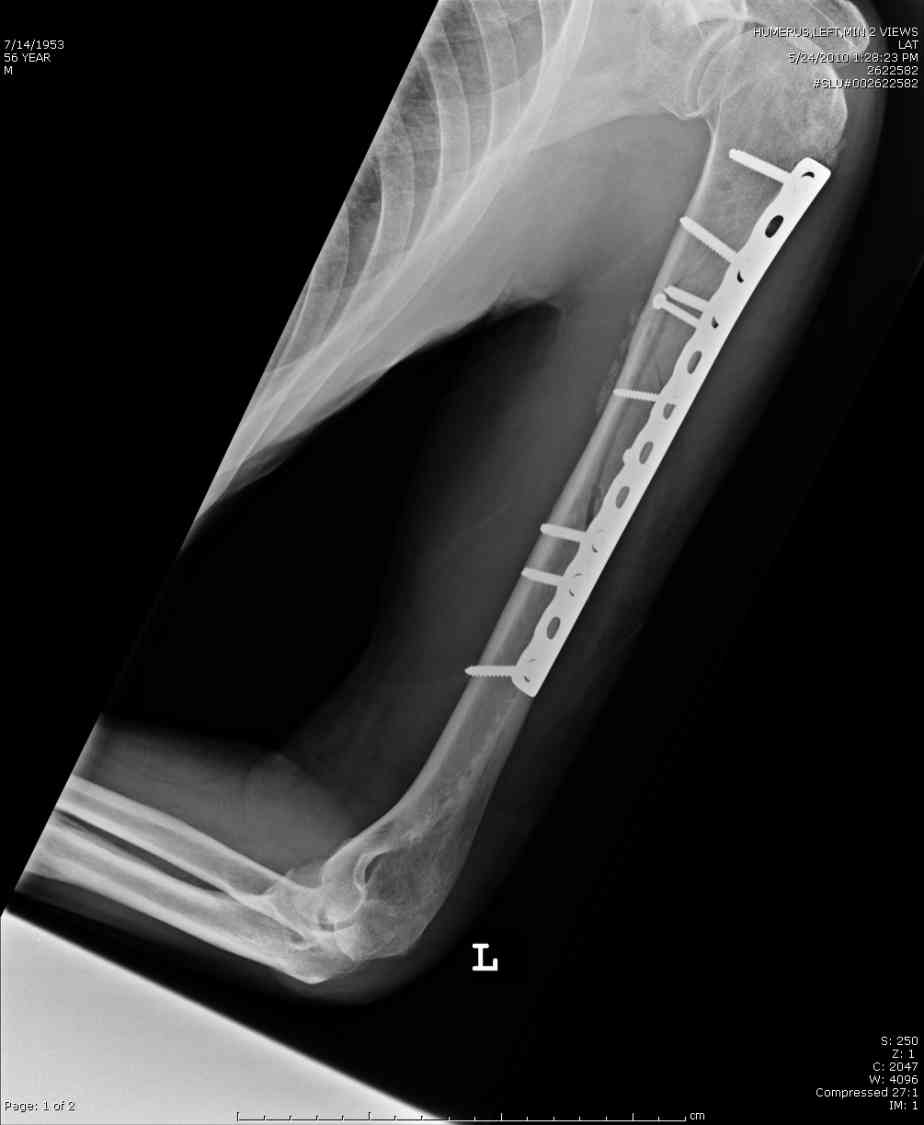

Кроме интрамедуллярного остеосинтеза, имеются другие варианты фиксации, наружный фиксатор и например здесь перелом плеча с повреждением нерва леченный открытым методом. Применен задний доступ с инспекцией нерва, межфрагментарная компрессия, фиксация узкой пластиной 4.5 мм.

Коллеги.

Для ознакомления